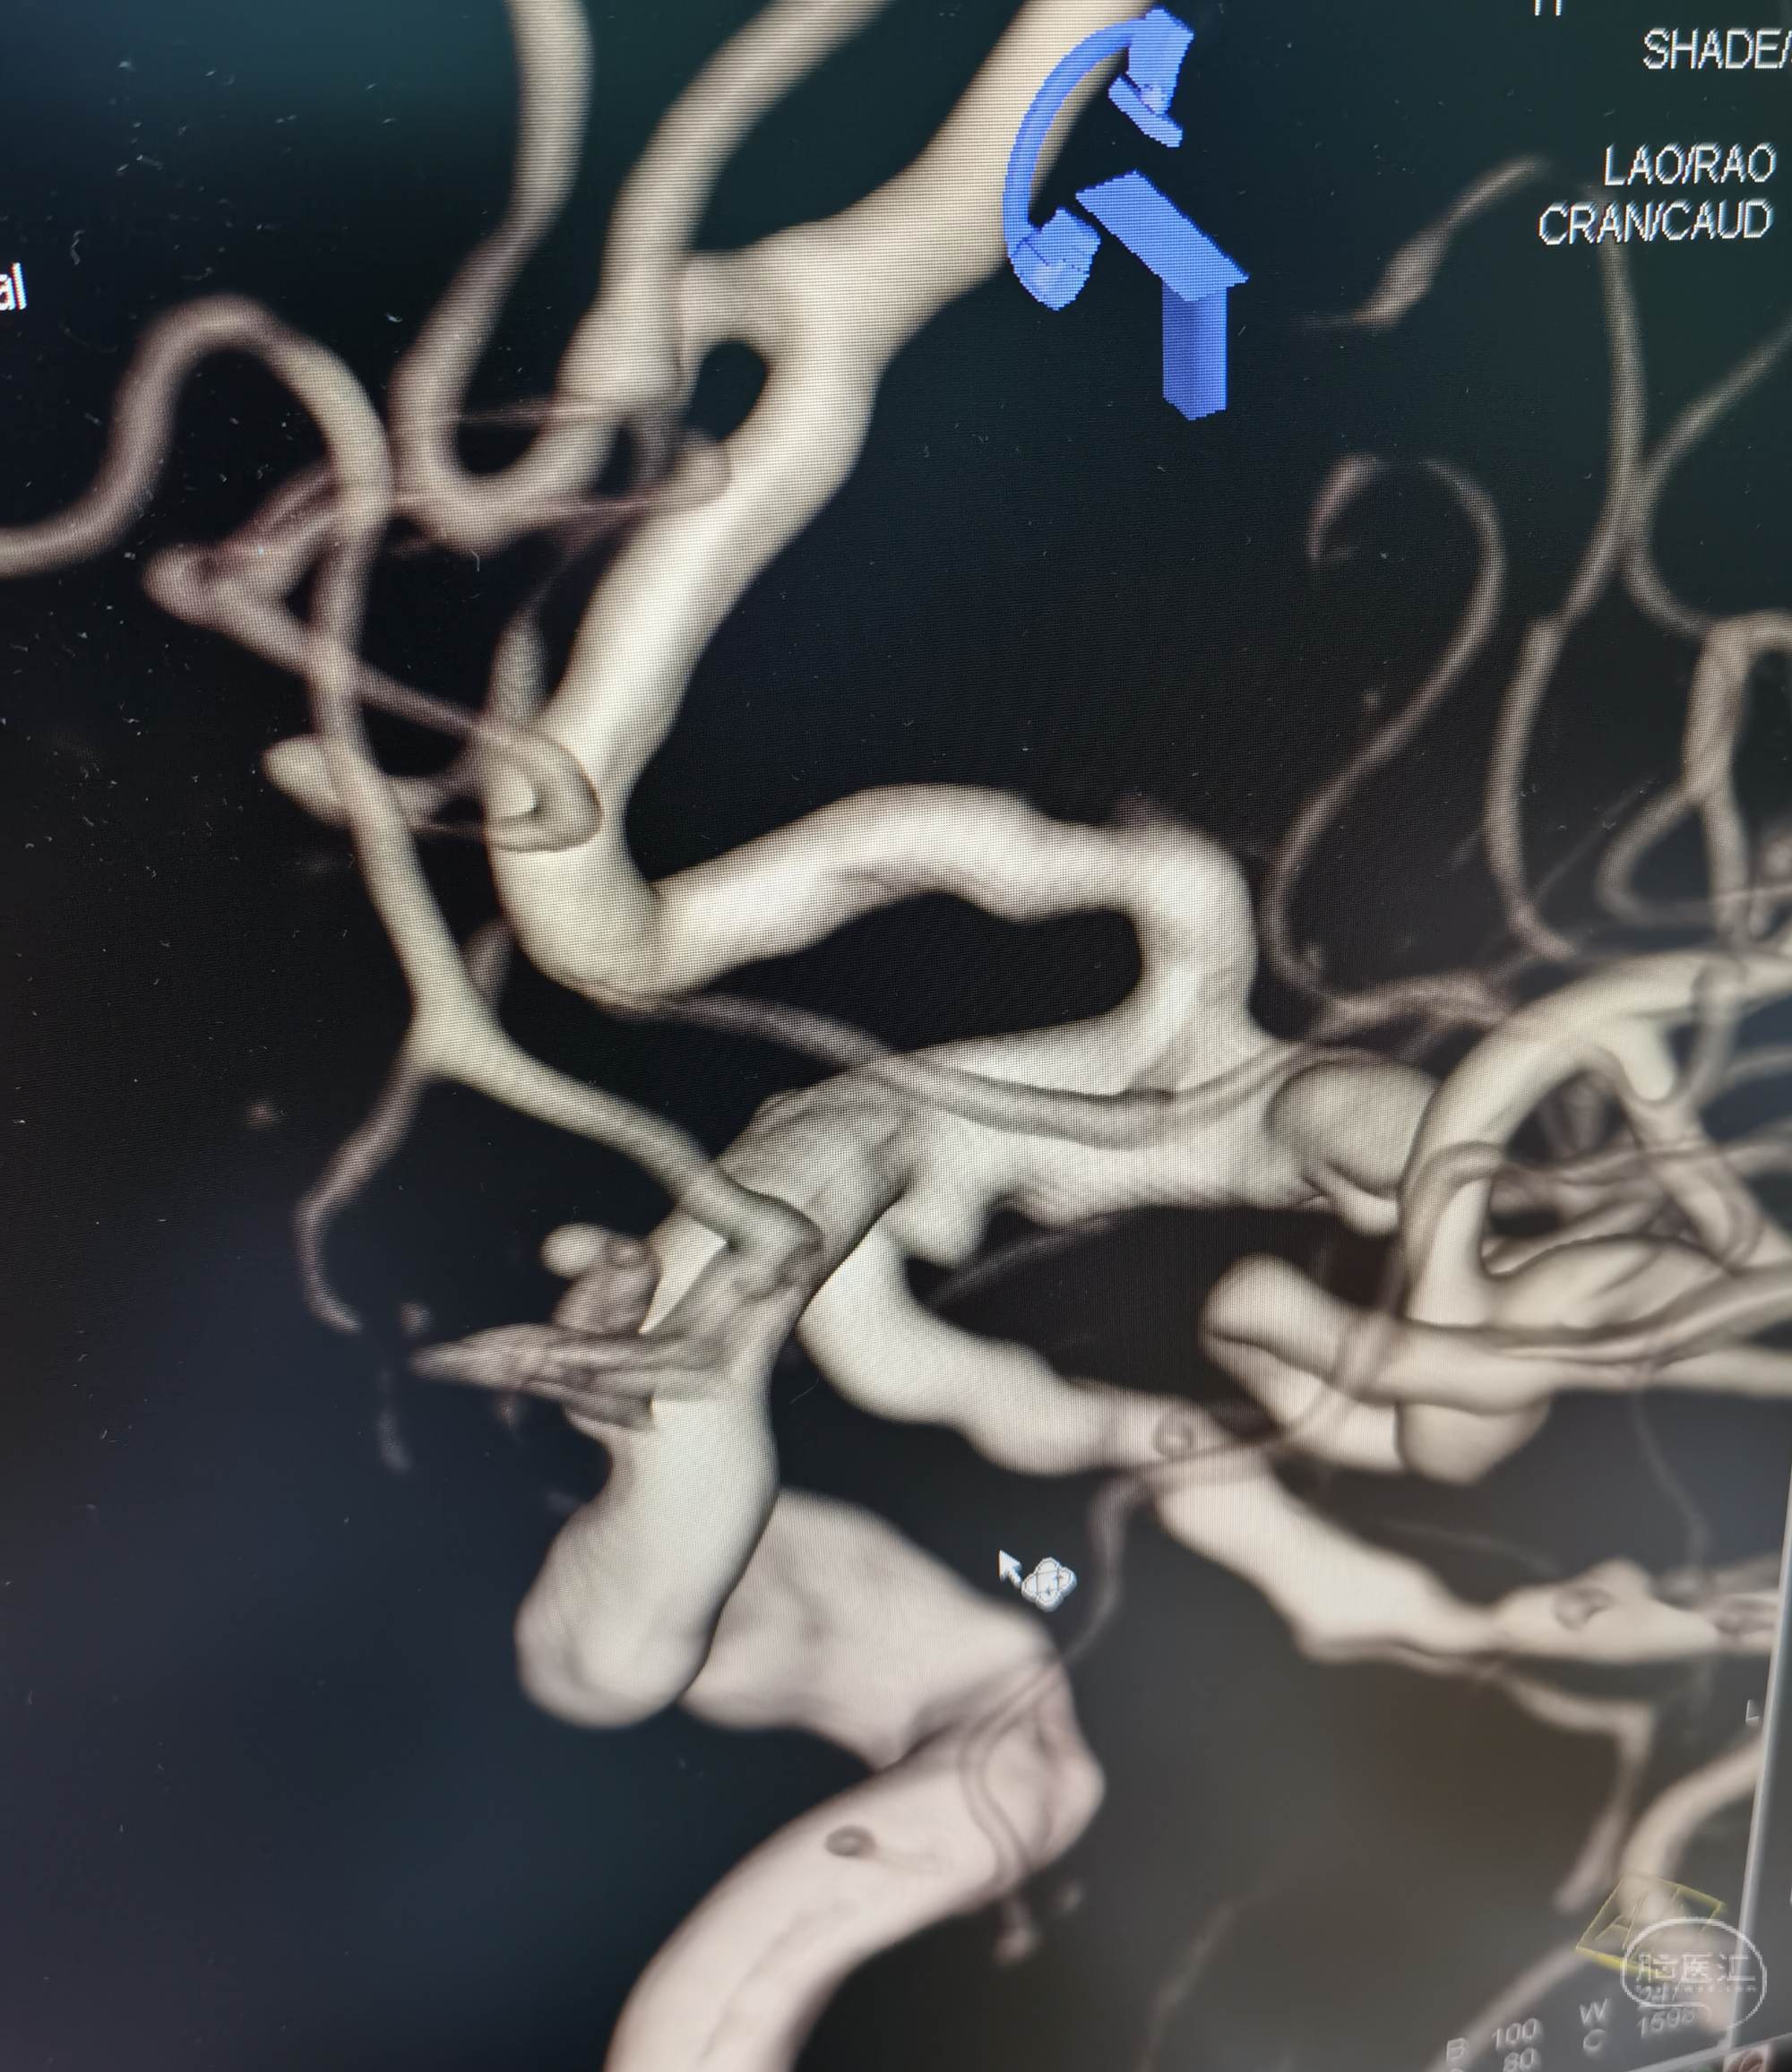

胚胎型后交通动脉。

压颈DSA造影示左侧P1缺如。